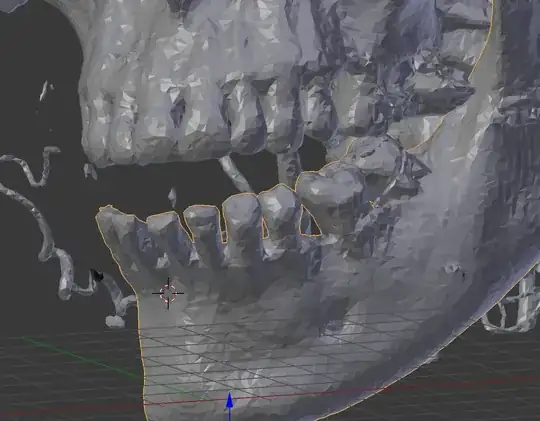

I'm trying to find, with the CT facial scan of a patient, the good position for his lower jaw, using his teeth. If I find his dental occlusion (when all teeth are in contact), I find the position.

The problem in blender is that teeth of the lower jaw go through the teeth of the upper jaw If I'm trying to do it manually.... There is always a spot where meshes are overlapping each other.

After manual repositioning, you can see the top of the front teeth overlapping...

The idea is to find the position where there is the highest number of meshes from the lower and the upper jaw in contact at the top of the teeth, but which don't join or overlap each other.